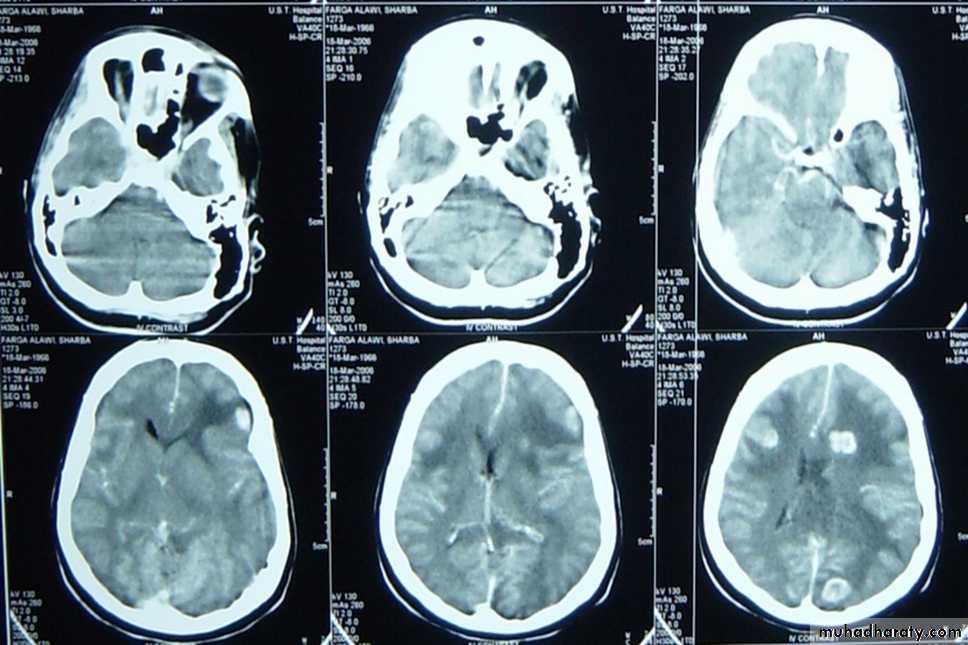

Focal (epidural hematoma-subdural hematoma-brain contussion-intracerebral hematomas-focal subarachnoid hematomaDiffused (subarachnoid hemorhage-diffused axonal injury-concussion)

Mostly resulting from meningial vessel tear (arteries > Veins > sinuses) and Fractures are common associated injury. Severe associated brain injury is rare. Usually the Level of consciousness is variable(lucidity interval is common). The haematoma with mass effect must be evacuated within ½ hour. if small follow up is recommended. The Prognosis depends on level of consciousness at time of presentation ( C picure is that of biconvex or lense hyperdense exrtracranial mass)

Cerebral contusions

It is a macroscopical focal laceration of brain tissue. Level of consciousness depends on size of contusion and location and the CT picure is that of irregular focal mixed densi intraaxial mass. Therec are 3 types, coupe, counter coupe and intermediate coupe). Small and deep ones needs follow upwhile Large with mass effect ones need lobectomy. the Large one may herniate as late as 9 days post trauma.Subarachnoid bleeding

CT scan : almost without exception , an unenhanced (i.e.- non – contrast ) CT scan of brain suffices for patients seen in emergency department presenting after trauma or with new neurological deficit .The main emergent conditions to rule out :

1. blood ( hemorrhages or hematomas(

a. EDH ( extradural hematoma (

d. intracerebral hemorrhage

7. shift of midline structures